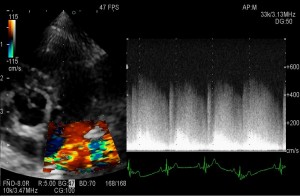

確定診断には心エコー検査が必要となり、肺動脈の分岐部での血液の乱流を確認します。

心エコー検査で肺動脈付近に血液の連続性の乱流を確認し、動脈管開存症であることを確認した。